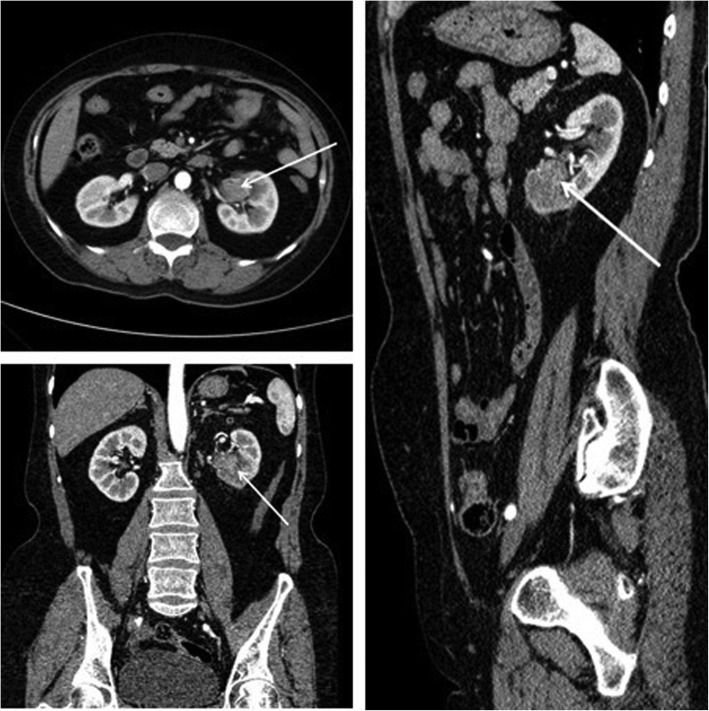

There were 45 patients in the test group, including 24 males and 21 females, 19 with left-sided tumors and 26 with right-sided tumors, and 31 with renal pelvic cancers while 14 with ureteral cancers. There were 44 patients in the control group, including 23 males and 21 females. The tumor location of 21 patients was on the left side while 23 patients were on the right side. There were 29 patients with renal pelvis cancer and 15 patients with ureteral cancer. All patients underwent computed tomographic urography (CTU) or magnetic resonance urography (MRU) before surgery to determine the tumor location (Fig. 1). Renal dynamic imaging and glomerular filtration rate (GFR) tests were performed to assess contralateral renal function. Thoracic and abdominal CT was performed to exclude tumor metastases, and cardiopulmonary function was assessed to exclude surgical contraindications. Visual analogue scale (VAS) was used to evaluate the degree of pain at 1 h, 12 h, 24 h, and 48 h after surgery. There were no statistically significant differences in the general conditions between the two groups, such as age, gender, tumor location, tumor stage, and grade (P > 0.05, Table 1).

Fig. 1.

Determination of the tumor location by CT. Arrows indicate an upper urinary tract urothelial carcinoma